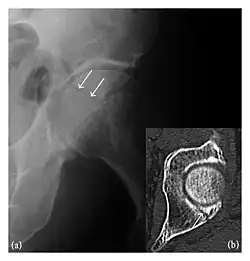

Occult osseous injuries may result from a direct blow to the bone by compressive forces of adjacent bones against one another or by traction forces during an avulsion injury. Lesions in the tibial plateau, hip, ankle, and wrist are often missed. In a tibial plateau fracture, any disruption of the posterior and anterior cortical rims of the plateau should be sought. Impaction of subchondral bone will appear as an increased sclerosis of the subchondral bone (Figure 1). In the hip, posterior acetabular fractures also present subtle radiographic findings. The acetabular lines should then be carefully examined keeping in mind that the posterior rim, which is harder to see on X-rays, is more frequently fractured than the anterior rim (Figure 2). In the wrist, detection of carpal bone fractures is often challenging, with up to 18% of scaphoid fractures radiographically occult. Carpal fractures, especially the scaphoid, are associated with the risk of avascular necrosis. In apparently normal wrist radiographs from symptomatic patients, if there is history of a fall on an outstretched hand with pain in the anatomic snuffbox, suggesting scaphoid injury, the initial examination with posteroanterior, lateral, and pronation oblique views must be complemented by other specific views such as supination oblique and the "scaphoid" view A careful examination of cortices for evidence of discontinuity or offset and cancellous bone for lucency is necessary (Figure 3).[1]

The greater tuberosity of the humerus is also an illustrative location of occult fractures. The osseous injury may follow seizures, glenohumeral dislocation, forced abduction, or direct impaction. They are commonly discovered on MRI in symptomatic patients with suspicion of rotator cuff tear. Coronal images are best suited for detection. They appear as crescentic oblique lines surrounded by a bone marrow edema pattern (Figure 5). The rotator cuff must be inspected since associated ligamentous lesions are common. In the ankle, malleoli and tarsal bones should be checked carefully for any cortical disruptions and radiolucent lines that may reveal a fracture. Awareness of the exact location of the pain will help direct the attention of the interpreter when searching for very subtle signs of fracture (Figure 6).[1]

Figure 6: Subtle anterior talar fracture in a 39-year-old man presenting with ankle pain after a fall. (a) Anteroposterior radiograph shows a subtle oblique radiolucent line through the talus (white arrows). (b) Sagittal CT reformation confirms the presence of an anterior talar fracture with cortical offset (black arrow). Avulsion fractures, which consist of a detached bone fragment resulting from a ligament or tendon pulling away from the bone, may also present with subtle radiographic signs. Tiny osseous fragments near the presumed attachment site of a ligament suggest this diagnosis. Common sites are the lateral tibial plateau (the Segond fracture), the spinal tuberosity of the tibia resulting from anterior cruciate ligament avulsion, and the ischial tuberosity.[1]